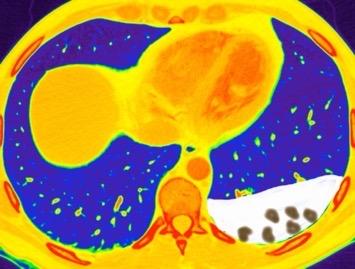

Hemorrágica………….30-70 UH

Extravasación iv. con sangrado activo……….>90 UH

“Simpático”………….,,,,<15 UH

Durso AM et al. Penetrating Thoracic Injury. Radiol Clin N Am 2015.

Urogénico……………….< 15 UH

Entérico.. ………………+/- 15UH

Biliar, Quiloso……………..<0 UH

Derrame no complicado + hematoma mediastínico

68 UH

Empiema pleural post-trauma

12UH

Abramowitz1 Y et al. Pleural Effusion: Characterization with CT Attenuation Values and CT Appearance .AJR 2008